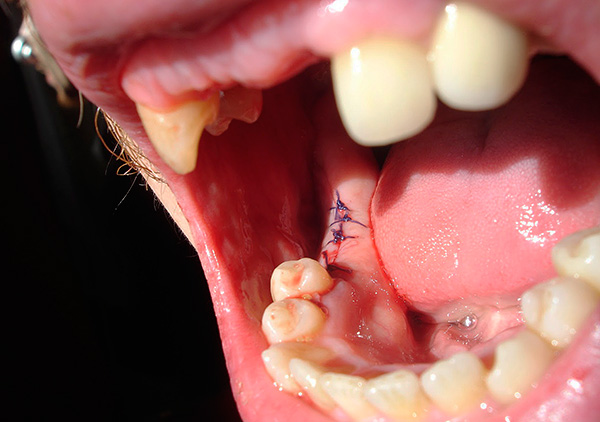

A imagem abaixo mostra um dente do siso retardado:

Etapas da extração dentária complexa:

- Preparação preliminar (pré-medicação, processamento do campo cirúrgico, etc.)

- Anestesia (geral ou local);

- Criando acesso ao dente extraído;

- Técnica instrumental para melhorar as condições de “luxação” das raízes dos dentes;

- Extração de raízes;

- Hemostasia;

- Preservação do orifício para preparar a implantação (como indicado);

- Sutura (de acordo com a situação);

- Nomeação de recomendações.

Criar ou melhorar o acesso a um dente envolve o uso de elevadores, um periotomo, uma espátula, uma broca com um conjunto de brocas e fresas e (raramente) um cinzel e um martelo. Depois que o acesso ao dente extraído é parcialmente criado (retração gengival, descolamento do retalho), o dente é removido pelo elevador e, se isso não for possível (como os retinados, por exemplo), o osso alvéolo é cortado por moagem na projeção da localização do dente. Ao mesmo tempo, o resfriamento é aplicado à área de preparação, uma vez que o tecido ósseo não deve superaquecer, caso contrário, ocorrerá necrose.

Quando o dente que está sendo removido se torna visível, o cirurgião pode começar imediatamente a usar elevadores para "pegá-lo". Muitas vezes, para facilitar a operação do dente, pode ser serrado (ou picado) em partes.